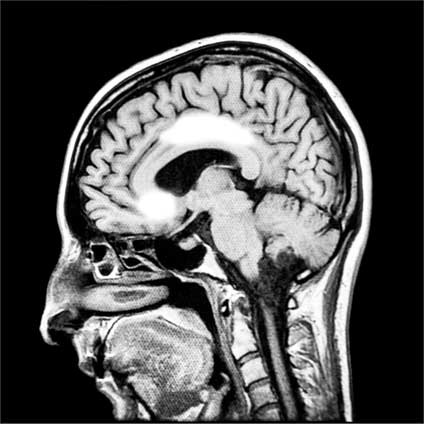

Сканирование мозга испытуемых показало, что отличие (рассогласование) во мнениях приводило к активации центральной части поясной извилины. При этом наблюдалось подавление активности прилежащего ядра. Таким образом генерировался сигнал ошибки, и в мозге возникала программа, направленная на изменение мнения, чтобы оно больше соответствовало мнению большинства.

Иллюстрация к книге — Мозг. Как он устроен и что с ним делать [i_057.jpg]

Рис. 57. Активация поясной извилины (белое пятно сверху) и подавление активности прилежащего ядра (белое пятно снизу) (по данным Klucharev et al., 2009)